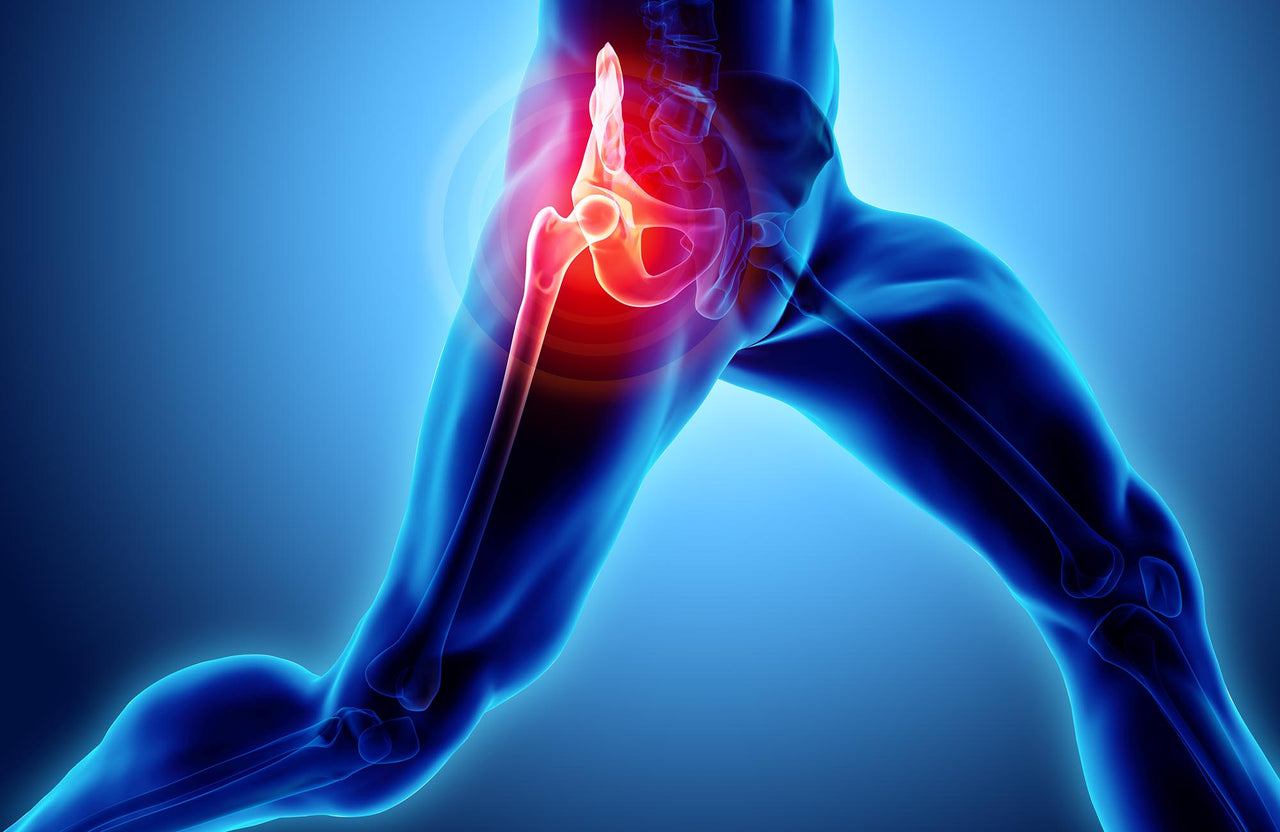

実際、こう感じて検索する方はとても多いです。運動後の股関節の痛みは、使った筋肉や関節まわりに負荷がかかったサインとして出ることがあると言われています。

痛みの出方は人それぞれで、「なんとなく重だるい感じが続く」「歩くとズキッとする」「脚を上げた瞬間に鋭い痛みが出る」など幅があります。タイミングもさまざまで、運動直後に違和感が出る人もいれば、翌日〜数日後に痛みを感じる人もいます。

「これって筋肉痛?」と思うケースも多いですが、股関節は体の中心に近く、複数の筋肉や関節が関わるため、太もも・お尻・鼠径部(足の付け根)など、痛む場所が少しわかりづらいのも特徴です。